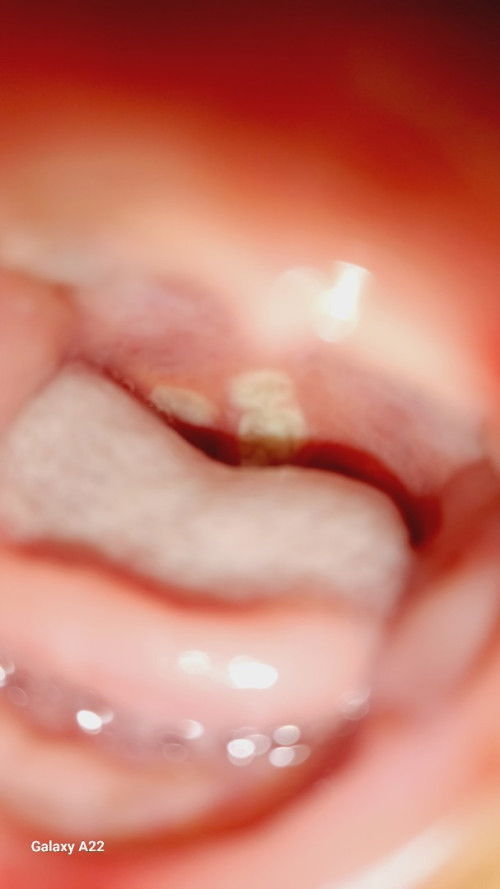

Anak saya baru tau bun kalau jamuren karena kami masih fokus ngobatin bibir dia yang pecah², saya kira nafsu mimiknya yang berkurang dan rewel dikarenakan bibirnya yang pecah², ternyata tidak bunda, waktu itu bibirnya sudah hampir sembuh tapi dalam hati saya kok anak saya masih rewel ya, terus nafsu mimik asinya berkurang harusnya kan meningkat karena bibirnya udya mulai sembuh, ternyata ya Allah kaget campur nangis, di dalam mulut anak saja ada sariwan seperti jamuran bunda, sudah saya bawa ke DSA di kasih obat mycostatin, udah jalan 3 hari ini bunda, kalau berubahan segi tidur, dia udah mulai tidur agak nyenyak, mimiknya mau walau sedikit², tapi putih²nya di dalam mulut masih ada bun, di kasih apa ya bun ada yang anaknya pernah gini ndk? Bingung sekali bun, dan kalud lihat anak sakit.